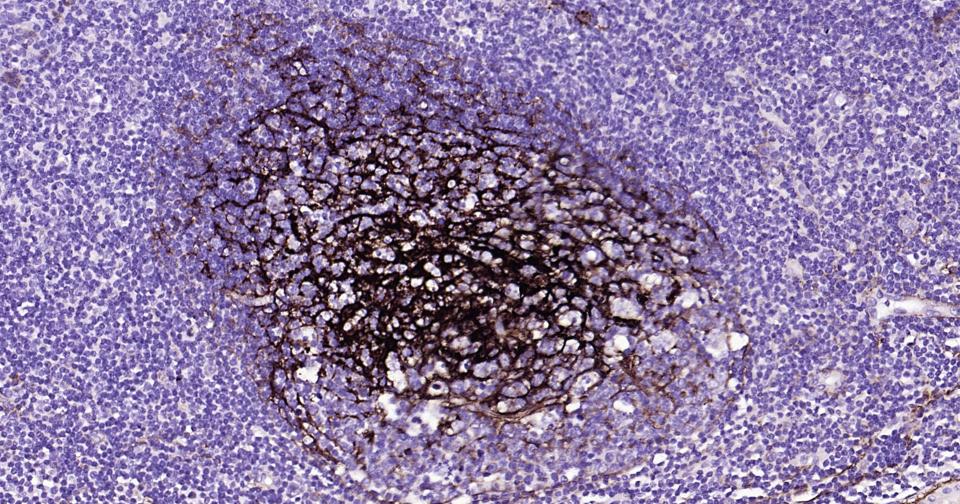

IHC-PHuman, Mouse, Rat1:100-500

IHC-FHuman, Mouse, Rat1:100-500

交叉反应: Human, Mouse, Rat